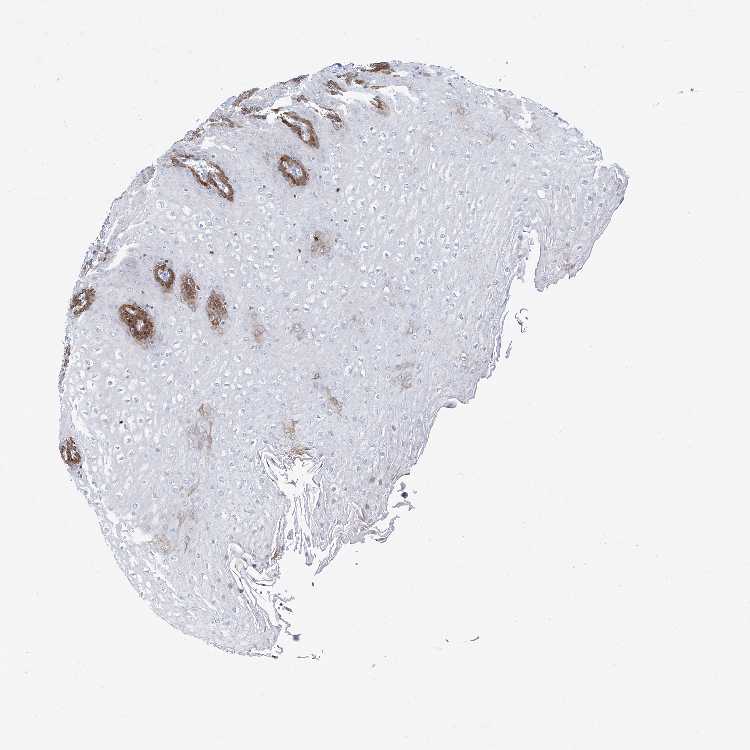

ESOPHAGUS - Antibody stainingi

Antibody staining in the annotated cell types in the current human tissue is reported as not detected, low, medium, or high, based on conventional immunohistochemistry profiling in selected tissues. This score is based on the combination of the staining intensity and fraction of stained cells.

Each image is clickable and will lead to virtual microscopy that enables deeper exploration of all samples and also displays staining intensity scores, fraction scores and subcellular localization as well as patient and tissue information for each sample.

Antibody HPA030162Antibody HPA030174

Squamous epithelial cells MediumLow